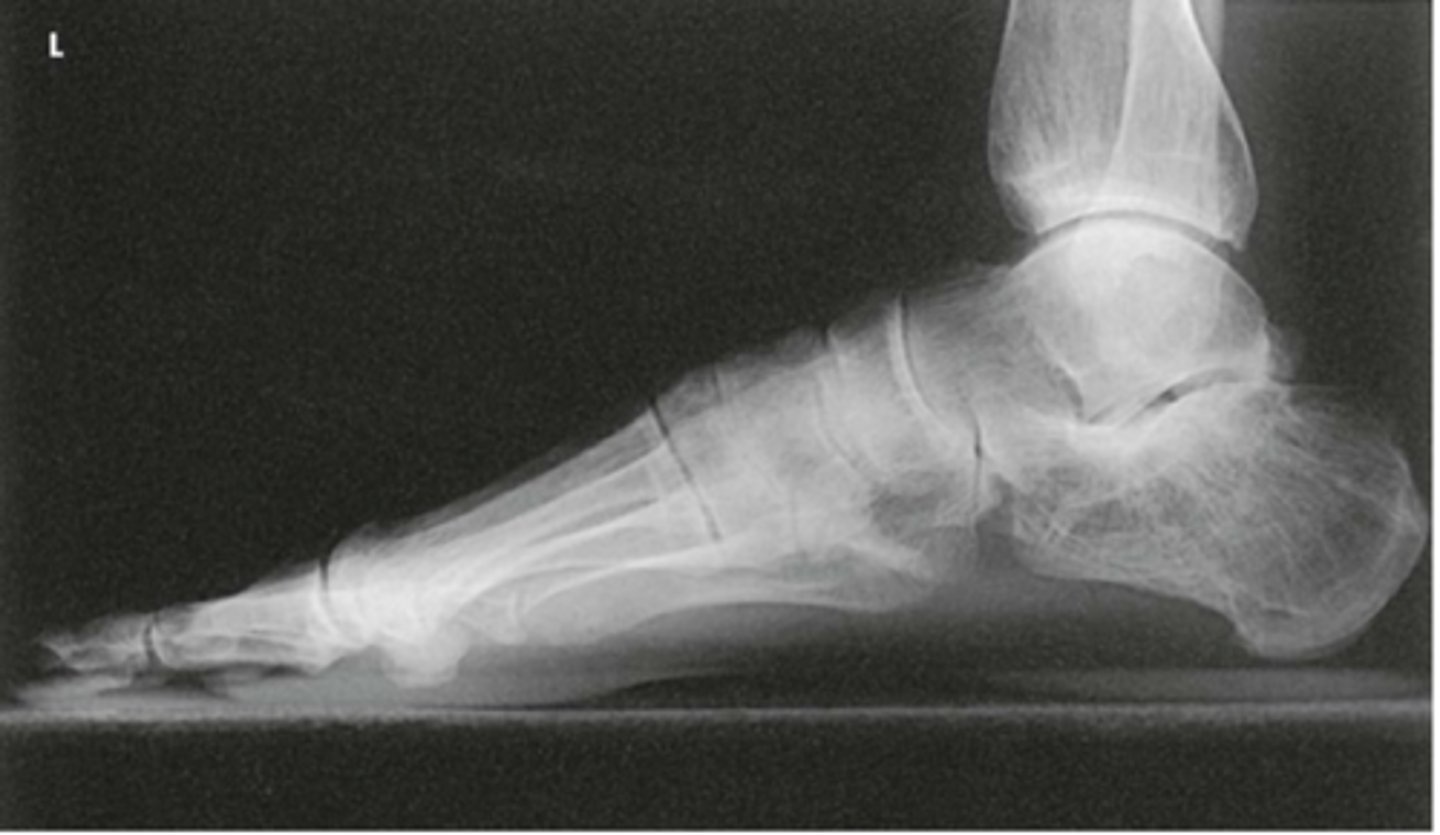

Lateral Weight Bearing Foot

What projection is this?

Evaluation Criteria for Lateral Weight Bearing Foot

- Horizontal beam

- Entire foot demonstrated

- Plantar surfaces of MTs superimposed

- Optimal exposure factors